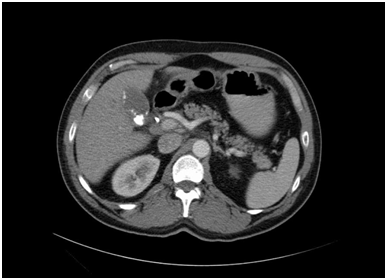

A 51-year-old Caucasian male presented to our emergency department with yellow skin, eyes and light colored stools which had developed over 2-3days along with some loss of appetite & weight. He was not complaining of any pain or change in his bowel or bladder habits. There was no associated fever, pain in the abdomen, nausea/vomiting or pruritus. His past medical history was significant for Diabetes Mellitus and Hyperlipidemia, which were being managed medically. The patient only admitted to occasional social drinking. Labs revealed an Obstructive Jaundice pattern with direct hyperbilirubinemia and elevated liver enzymes. Previous records showed normal LFTs despite statin therapy for Hyperlipidemia. US abdomen showed presence of gallstones and GB sludge. CT Abdomen done in the emergency room showed multiple calcified gallstones within the Gall Bladder and a large gallstone at the neck of the Gall Bladder (Figure 1). There was also mild intrahepatic biliary ductal dilatation noted in the CT scan. The hepatitis panel was non-reactive for Hep A, B and C, ANA was negative and SMA was 1:20. Further labs revealed an elevated CA 19-9 level. Working diagnosis at this time involved choledocholithiasis with autoimmune etiology vs Mirizzi syndrome MRCP showed a large GB stone within the neck of the gall bladder with asymmetric biliary ductal dilatation. MRI abdomen (Figure 2) confirmed the GB neck gallstone and showed the stone exerting the mass effect on the adjacent CBD contributing to the dilatation of the intrahepatic biliary system superior to the level of the obstruction consistent with Mirizzi syndrome type I.

Figure 2 CT scan image showing the obstructing gall stone at the neck of the gall bladder.